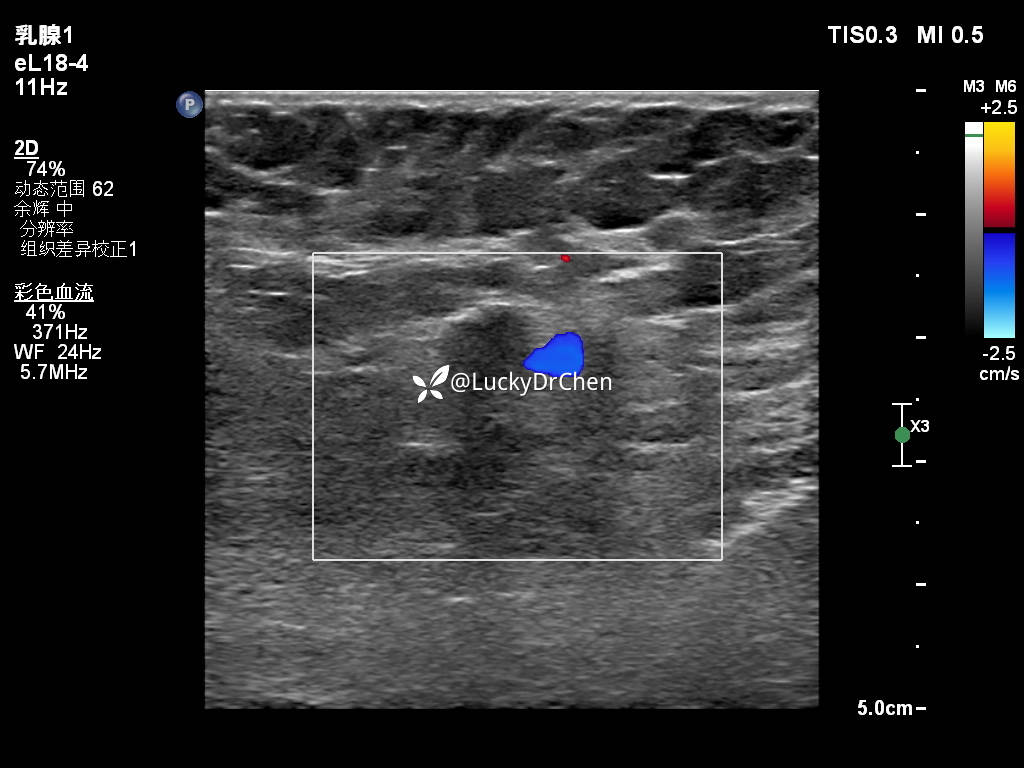

腋下肿大淋巴结